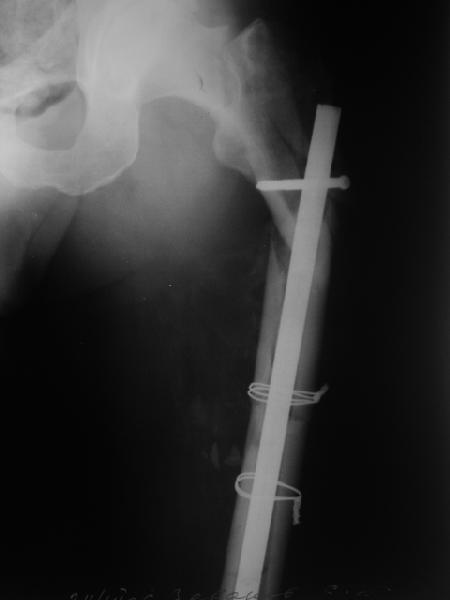

В общем, сделали. См. приложение.

Длина и из-за этого ось получились не совсем такие, как хотелось бы, все-таки срок после той операции уже 6 недель. Может быть, стоило провести дистракцию аппаратом неделю-другую. Заранее спасибо за комментарии и критику.

Александр, поздравляю от души, отличная работа, вообще-то и у меня тоже были опасения по поводу латеральной стенки. Идеальное показаниt к применению импланта закрытым методом при таких переломах, когда болт замыкается в штифте, конструкции придается угловая жесткость, примерно как в Blade Plate.

Точно. Плюс длина диафизарной части больше, чем у blade plate, и плечо рычага короче, чем у накостных фиксаторов.

Проксимальный фрагмент весь разрушен, и эти два фиксатора нужно было как-то соединять, винты через пластину чтобы прошли через отверстия в стержне. Это было бы и труднее, и устойчивость все-таки меньше, чем у гвоздя проксимального типа.